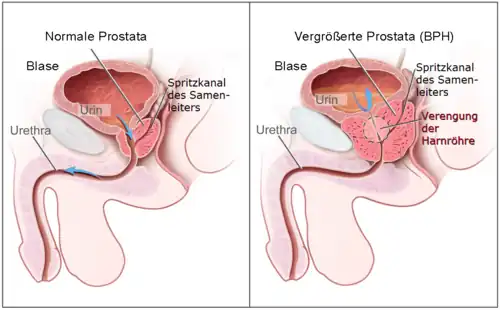

Eine gutartige Vergrößerung der Prostata (Vorsteherdrüse) – auch bezeichnet als Benigne Prostatahyperplasie (BPH) – entsteht durch Vermehrung ansonsten unauffälliger Zellen. Frühere Bezeichnungen sind auch Prostataadenom (PA) oder fälschlich benigne Prostatahypertrophie.

Zu einer BPH kommt es gewöhnlich bei Männern im mittleren bis höheren Lebensalter. Es handelt sich um eine Vergrößerung von Prostatadrüse und Anteilen des Zwischengewebes, die zumeist von der sogenannten Übergangszone ausgeht. Ein Krankheitswert kommt dieser gutartigen Drüsenvergrößerung nur bei gleichzeitigem Auftreten von Symptomen zu (wie z. B. nächtlichem Wasserlassen, Harnverhalt oder abgeschwächtem Harnstrahl bei gleichzeitig massiv erhöhtem Blasenentleerungsdruck). Die Krankheit ist mittels moderner Methoden gut behandelbar. Unbehandelt kann die Prostata aber grundsätzlich so lange wachsen, bis sie den Blasenauslass völlig verschließt. Durch den Verschluss kann die Niere nicht mehr ausscheiden (postrenales Nierenversagen), was zum Tod durch innere Vergiftung bei Urämie führt.

Die Harnröhre verläuft unterhalb der Blase ein Stück weit durch die Vorsteherdrüse. Diese besteht aus einem linken und rechten Lappen sowie einem hinter der Harnröhre gelegenen Anteil, der als Isthmus prostatae oder als Mittellappen bezeichnet wird. Eine BPH entsteht durch eine Zellvermehrung in der sogenannten Übergangszone und den um die Harnröhre herum angelegten (periurethralen) Drüsen. Dabei vermehren sich jedoch nicht ausschließlich die Drüsenzellen, sondern auch Bindegewebe und Muskelzellen – deshalb ist auch der früher geläufige Begriff Prostataadenom fachlich nicht korrekt. Bei entsprechend ausgeprägter Vergrößerung wird dabei die periphere Zone der Prostata – sie macht normalerweise drei Viertel der Organmasse aus – nach außen abgedrängt und dabei so weit gedehnt, dass sie im Schnittbild das Organ nur noch als dünne Schicht, die sogenannte chirurgische Kapsel, umgibt. Der Isthmus prostatae (Lobus medius, Mittellappen) kann sich zudem weit in das Blaseninnere vorwölben.

Das Gewicht der Prostata beträgt normalerweise etwa 20 bis 25 Gramm. Bei Vorliegen einer BPH wiegt die Prostata 30 bis 150 Gramm. In der Summe stellt die BPH ein Hindernis für den Harnabfluss aus der Blase dar (subvesikale Obstruktion, also unterhalb der Harnblase). Bei normalem Miktionsdruck (Druck, den die Blasenwand aufbaut, um den Harn auszutreiben) ist dann die Harnflussrate reduziert. Ein kompensatorisch erhöhter Miktionsdruck kann zu einer Balkenblase oder autonomen Detrusorkontraktionen (Overactive Bladder, OAB) führen.[10][11] Zusätzliche Bedeutung kommt dem sich in das Innere der Harnblase vorwölbenden (daher im klinischen Sprachgebrauch auch als intravesikal gelegen bezeichnet[12]) vergrößerten Mittellappen zu, der den Blasenausgang verlegen kann. Dieser Effekt kann unabhängig von der unterhalb der Blase bestehenden Einengung der Harnröhre auftreten.